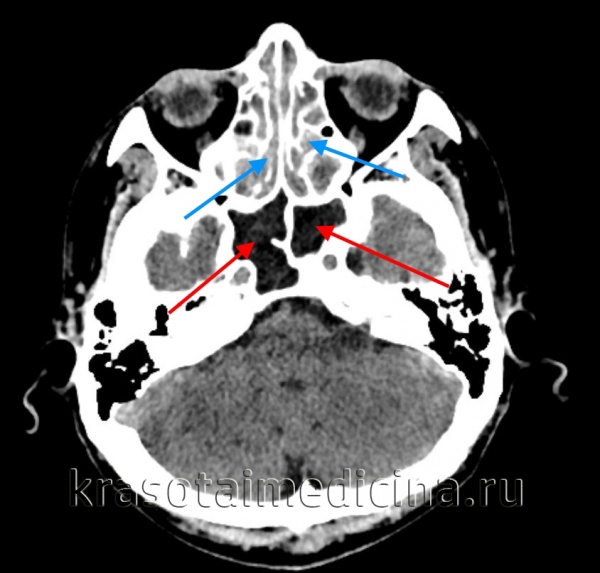

КТ ППН. Полипозный пансинусит. Отек слизистой оболочки верхнечелюстных пазух (красная стрелка), полиповидные образования в в/челюстных пазухах (синяя стрелка), выраженное снижение пневматизации полости носа (зеленая стрелка).